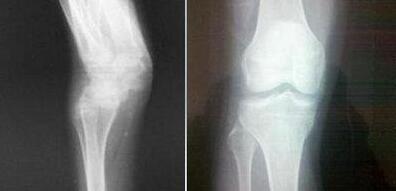

(图:从X光片上可明显看出王先生的膝关节已恢复正常)

治疗后:王先生在第一次疗程治疗后,本来习惯地吃点药,可是他感觉自己关节正常不痛了,根本就不用像以前药不离手,止痛药也不用吃。在治疗三个疗程后,王先生已经感觉关节肿痛在逐渐减轻。关节肿胀疼痛也消失不见了,各项检查数据都恢复正常水平。